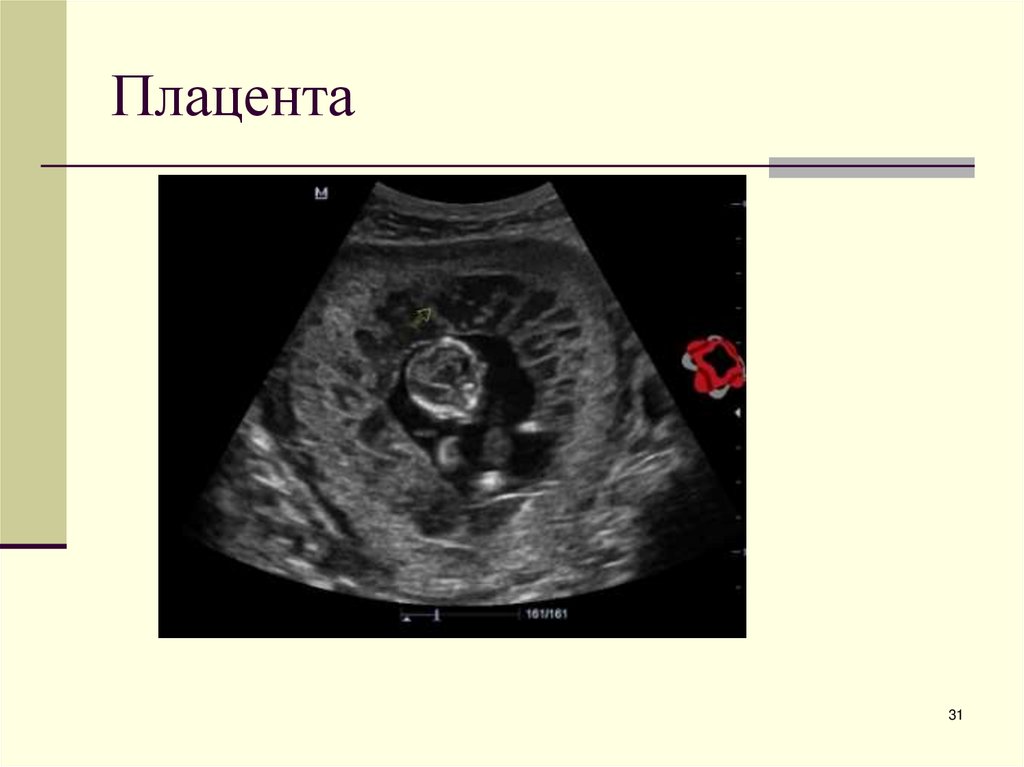

31. Плацента

31